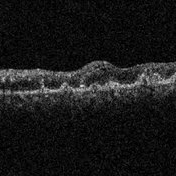

Behcet's Disease Behcet's DiseaseMar 13 2013 by Hamid Ahmadieh, MD Late phase FA of the left eye of a 23-year-old man with retinal vasculitis due to Behcet's disease . Photographer: Solmaz Shahmohammad, Negah Eye Center, Tehran Imaging device: Heidelberg Spectralis Condition/keywords: retinal vasculitis